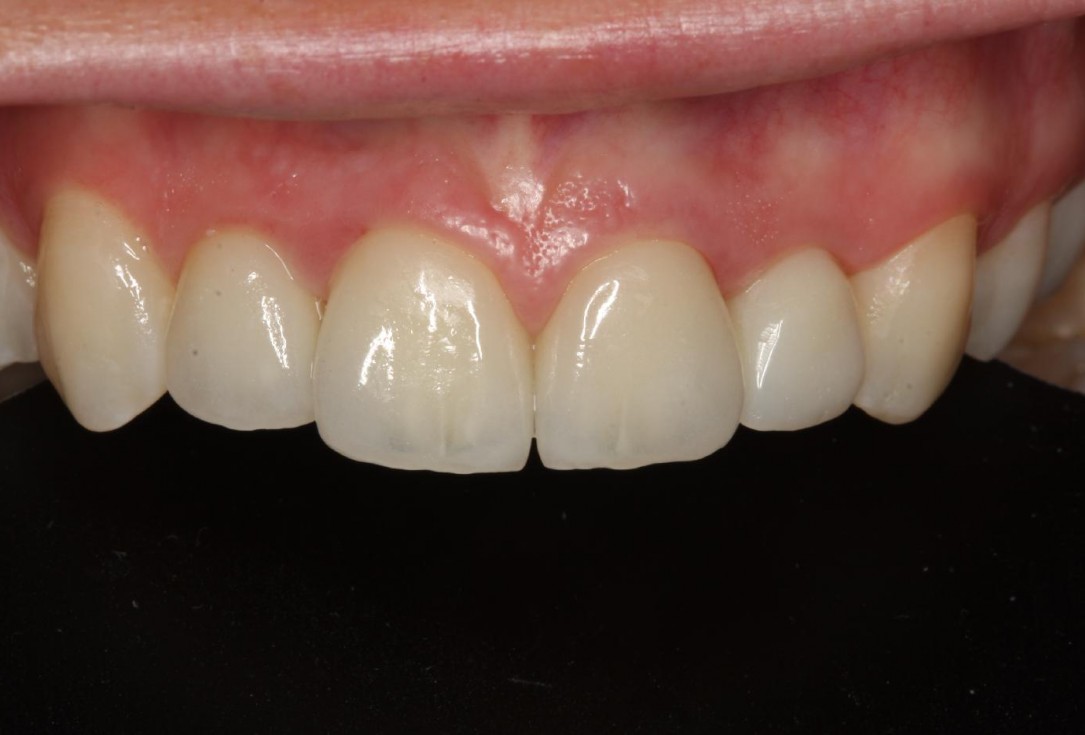

12/12 - Final outcome 18 months post-operativeSoft tissue thickening at immediate implant placement and GBR with mucoderm® and maxgraft® - Dr. A. Puisys